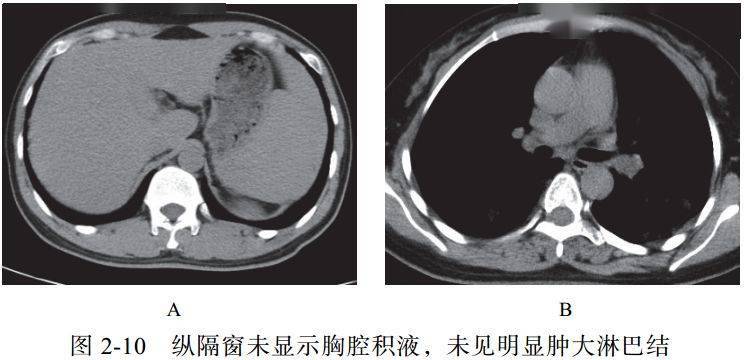

(十)阴性征象

新冠肺炎早期病灶内部未见明显空洞和肺气囊形成,极少见到树芽征;双侧胸腔未见明显积液;一般未见明显纵隔淋巴结肿大(图 2-10)